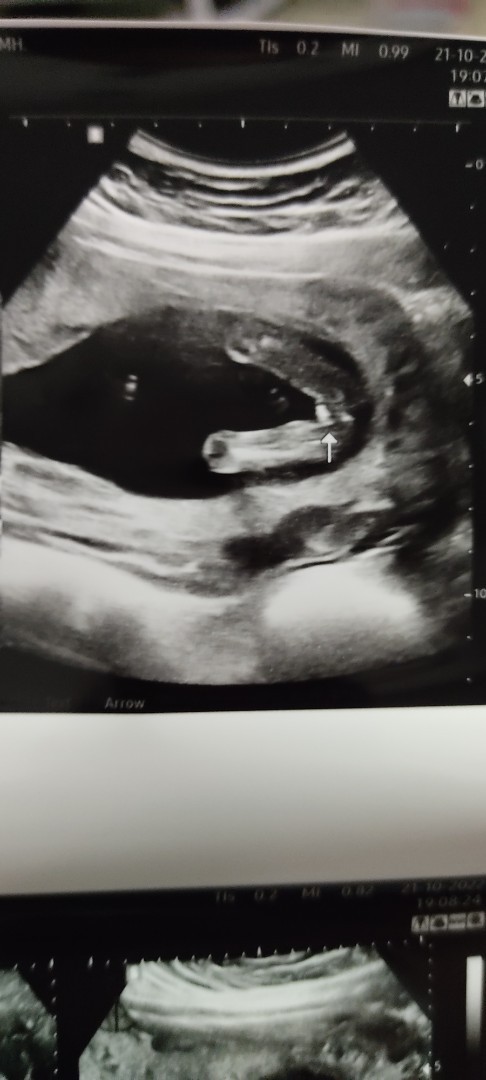

หญิงค่ะ เป็นกรีบเลยค่ะแม่

ไข่มาเต็มจอเลยค่ะบ้านนี้

บ้านนี้หญิงจร้า